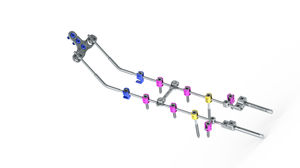

... El sistema cervical posterior Prodorth ofrece múltiples tornillos, ganchos, varillas con puntas hexagonales, varillas de transición, placas occipitales y diferentes tipos de conectores para adaptarse mejor a la anatomía del paciente. Tornillos ...

... neon³ es un sistema modular de varilla-tornillo para la estabilización dorsal de la columna vertebral humana desde la región de transición occipitocervical hasta la región torácica superior. -Elevada estabilidad desde ...

... Fabricado en aleación de titanio 3.tornillos poliaxiales de 5 mm y 4,0 mm Tornillos pediculares, tornillos de vástago liso, tornillos de masa lateral Varillas rectas y precurvadas de 30mm a 400mm Varillas dobles disponibles desde varilla de 3.5mm con ...